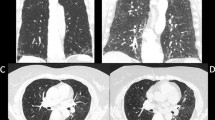

As regards Warrick’s score, the total score mean ± SD was 17.38 ± 5.90 ranging from 7 to 29. Alveolitis score and fibrosis score were 2.99 ± 1.07 and 14.40 ± 5.32 respectively. Severity score and extent score were 8.63 ± 3.75 and 8.63 ± 3.08 respectively. GGO, irregular pleural margin, subpleural cyst, honeycombing, and septal and subpleural lines were found in 96.6%, 70.8%, 55.1%, 49.4%, 48.3% of the patients respectively (Table 4).

Patients with GGO in HRCT showed a significant decrease in DLCO-SB than patients without GGO in HRCT chest (43.3 ± 18.17 versus 68 ± 12.12) with P value 0.022. Also, a highly significant decrease in DLCO-SB was noted in patients with subpleural cyst and honeycombing with P value 0.001 and 0.002 respectively (Table 9).

Decline in spirometric indices and DLCO-SB were associated significantly with the different radiological patterns of CT chest. FVC was significantly decreased in patients with honeycombing and subpleural cyst in HRCT. Highly significant decrease in FEV1 was noted in patients with subpleural cyst. Also, this work demonstrated a highly significant decrease in DLCO-SB in patients with subpleural cyst and honeycombing and a significant decrease in DLCO-SB in patients with GGO.